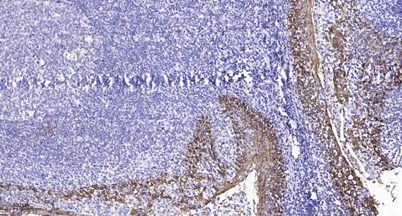

Product name: TDE1 rabbit pAb

Dilutions: Western Blot: 1/500 - 1/2000. Immunohistochemistry: 1/100 - 1/300. Immunofluorescence: 1/200 - 1/1000. ELISA: 1/20000. Not yet tested in other applications.